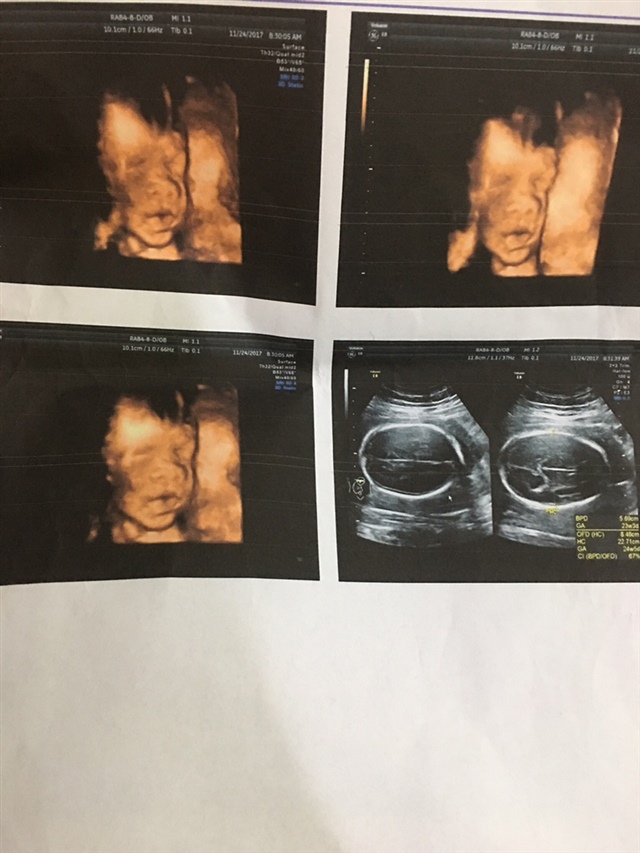

孕22周+1天

好漂亮,肯定是个听话的宝宝

对啊,[帖主]:第一眼看到b超单觉得丑死了,现在看习惯了觉得还顺眼起来了😆